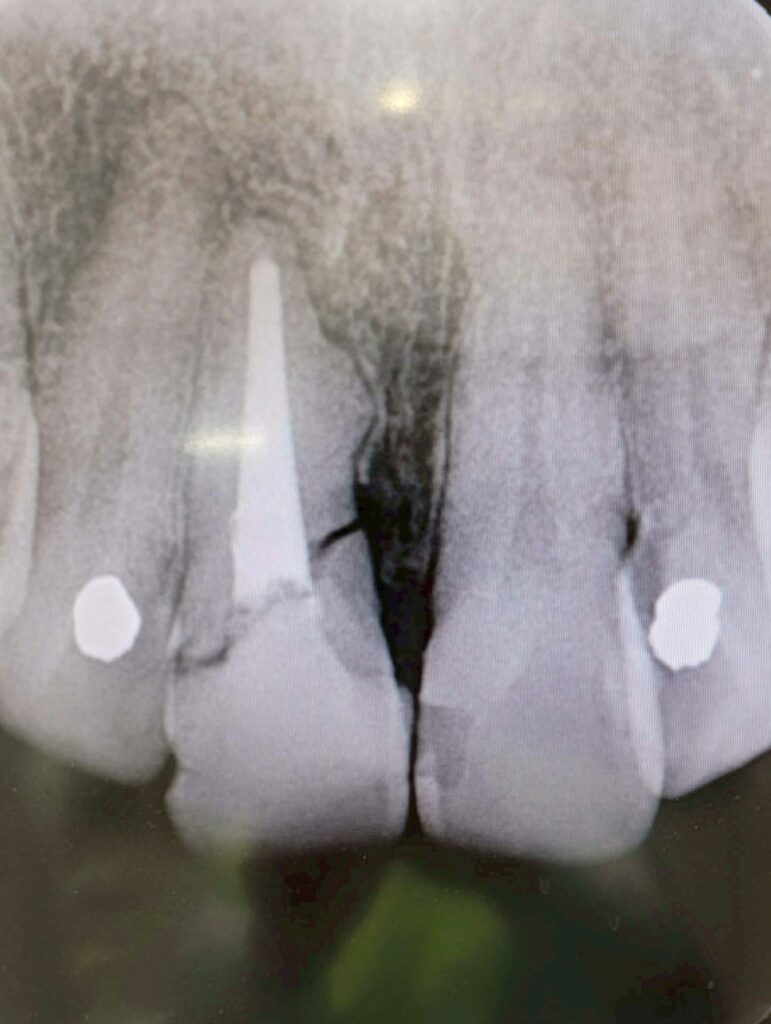

実際に確認すると、前歯に水平破折を認めます。

この状態では、長期的な予後を考えると抜歯+インプラント治療が第一選択になるケースが多いのは事実です。